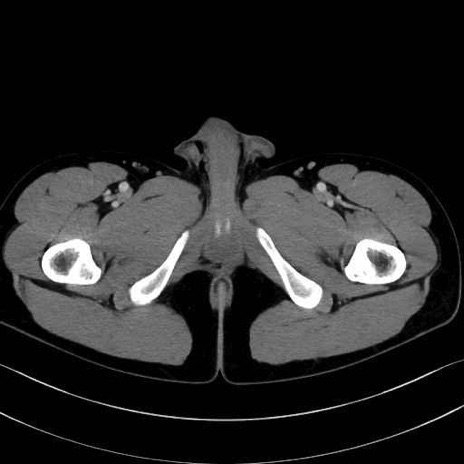

精嚢(seminal vesicle)のCT画像における解剖

症例

【症例】20歳代 男性 スクリーニング